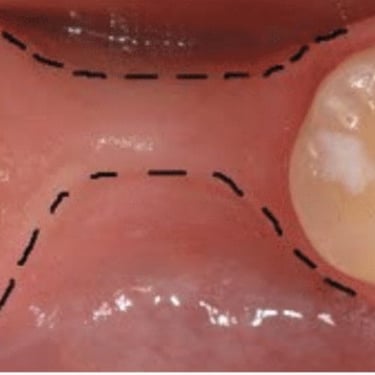

Atrofia ósea alveolar

La atrofia ósea alveolar es la pérdida de hueso en la mandíbula o el maxilar debido a la ausencia prolongada de dientes.

Los pacientes pueden notar que sus encías están hundidas y que las dentaduras no encajan bien.

El tratamiento puede incluir injertos óseos para preparar el sitio para la colocación de implantes.